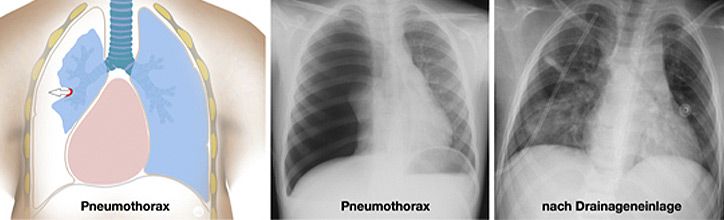

Kirschner-Draht-Osteosynthese

Andere Verfahren der operativen Frakturversorgung im Kindesalter sind die Kirschner-Draht-Osteosynthese, die Verschraubung, der Fixateur und die Plattenosteosynthese. Metallentfernungen werden ambulant durchgeführt, Nachuntersuchungen zum Ausschluss etwaiger Wachstumsstörungen erfolgen in unserer Frakturensprechstunde.